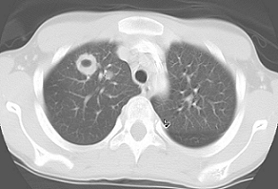

![]()

Main Tx for this condition

PJP: Tx IV Bactrim